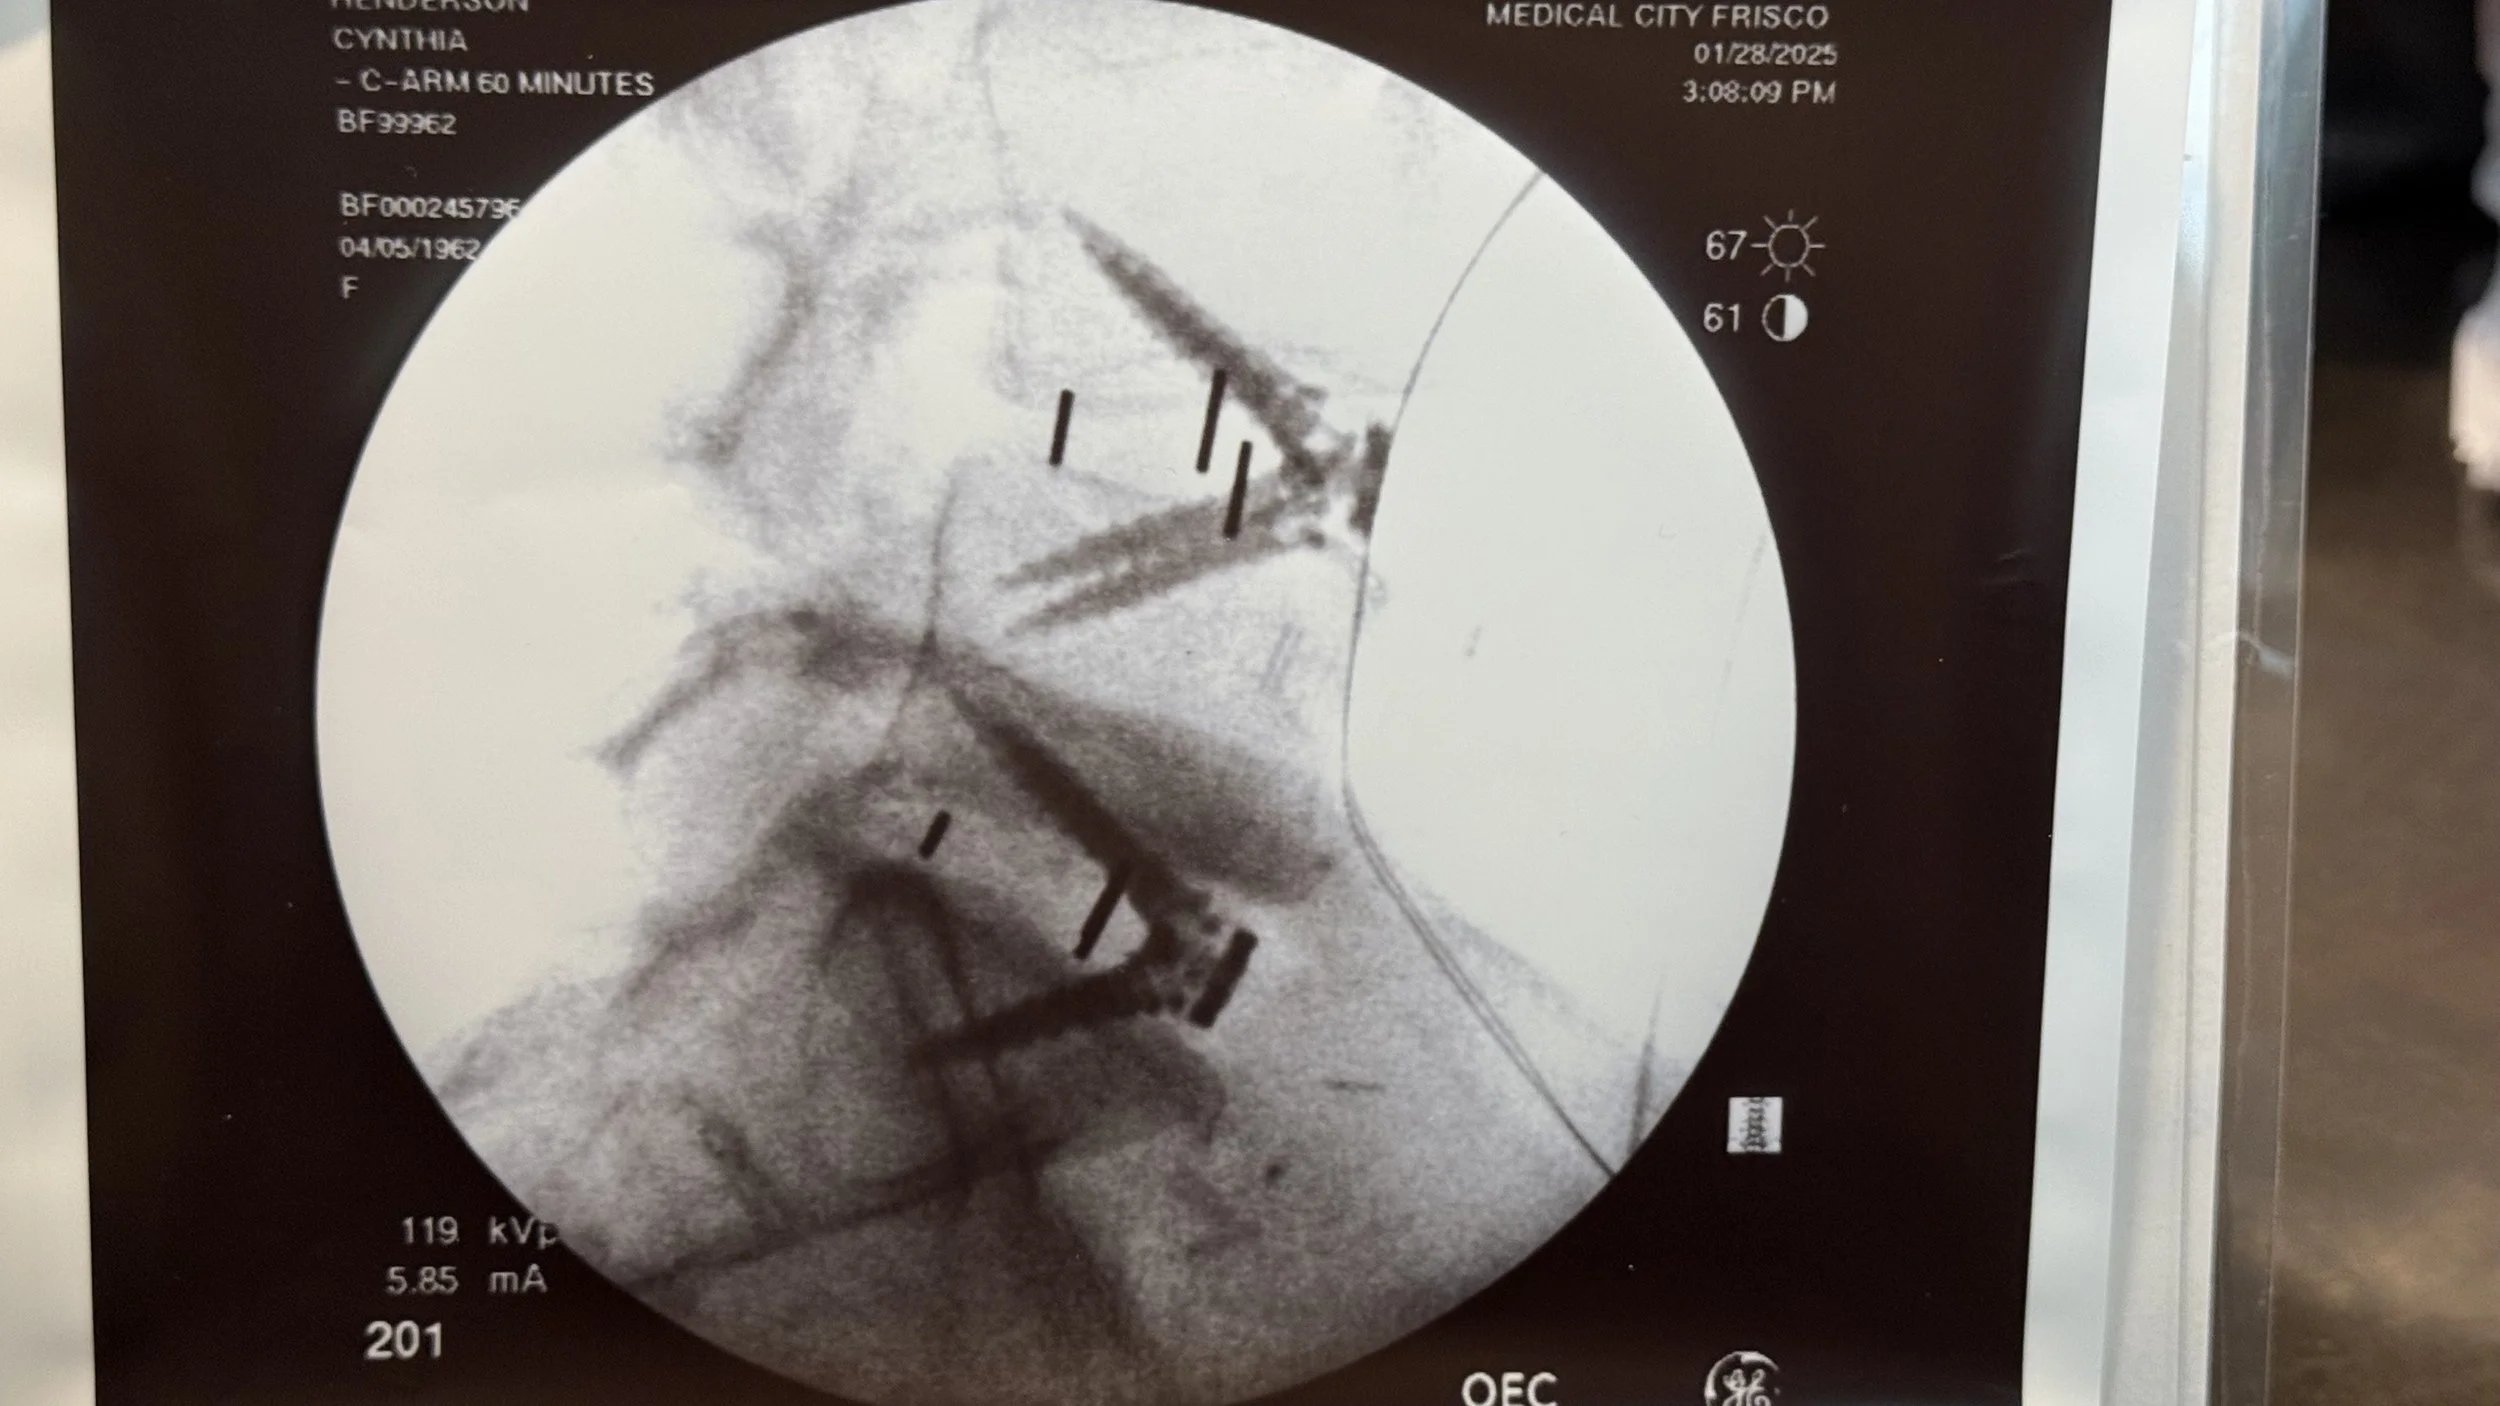

Next